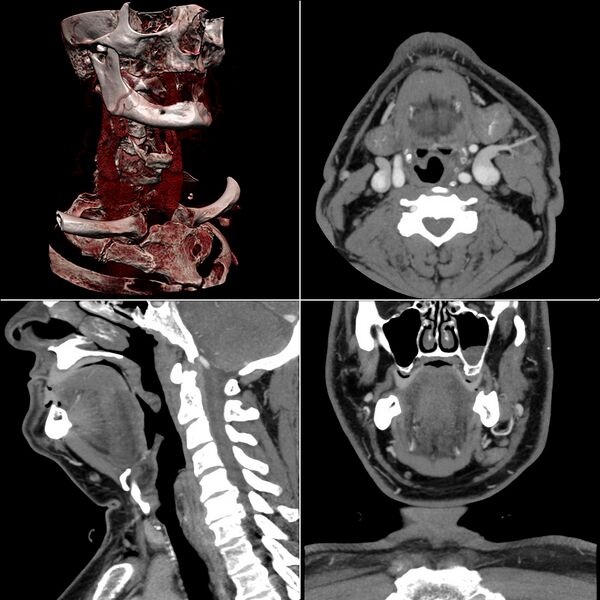

Изображения, полученные методом рентгеновской компьютерной томографии, имеют свои аналоги в истории изучения анатомии. В частности, Николай Иванович Пирогов разработал новый метод изучения взаиморасположения органов оперирующими хирургами, получивший название топографической анатомии. Сутью метода было изучение замороженных трупов, послойно разрезанных в различных анатомических плоскостях («анатомическая томография»). Пироговым был издан атлас под названием «Топографическая анатомия, иллюстрированная разрезами, проведёнными через замороженное тело человека в трёх направлениях». Фактически, изображения в атласе предвосхищали появление подобных изображений, полученных лучевыми томографическими методами исследования. Разумеется, современные способы получения послойных изображений имеют несравнимые преимущества: нетравматичность, позволяющая проводить прижизненную диагностику заболеваний; возможность аппаратного представления в различных анатомических плоскостях (проекциях) однократно полученных «сырых» КТ-данных, а также трёхмерной реконструкции; возможность не только оценивать размеры и взаиморасположение органов, но и детально изучать их структурные особенности и даже некоторые физиологические характеристики, основываясь на показателях рентгеновской плотности и их изменении при внутривенном контрастном усилении.

КТ-ангиография позволяет получить послойную серию изображений кровеносных сосудов; на основе полученных данных посредством компьютерной постобработки с 3D-реконструкцией строится трёхмерная модель кровеносной системы.